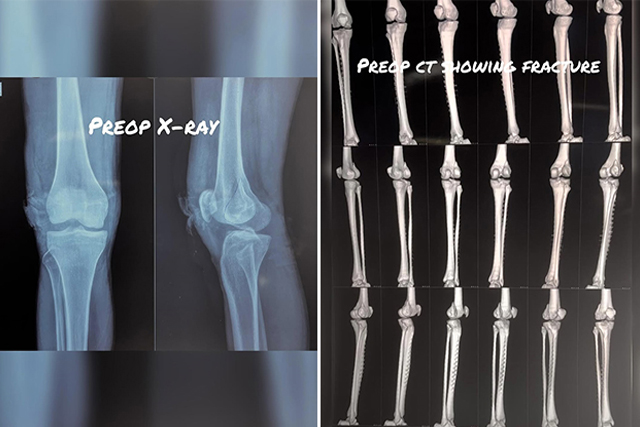

Open reduction and internal fixation (ORIF) for severe proximal tibia fracture